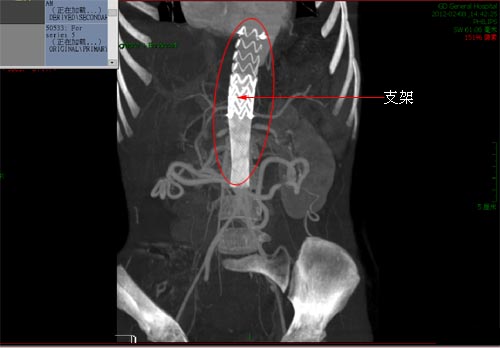

彭林主任介绍说,介入微创置入支架是唯一可行方法。这类手术国际报道不超过10例,国内无此类手术作为参考。血甲疝外科进行了大胆的尝试,置入大于患儿血管直径的支架堵住破洞。这是考虑若放置与患儿血管同样大小支架,则可能随着患儿的生长,支架可能脱离。

手术方案可行,关键是如何准确、快速放置支架,稍有迟疑极易导致肾血管,肠系膜上血管,腹腔干大血管堵塞,极易导致双肾,小肠,部分结肠等腹腔器官缺血坏死,死亡风险极大。由于小儿血管细小,对手术精细度要求极高,若相差一个公分的误差都可能导致以上情况发生。随着超硬导丝的支架引入,逐步的张开支架,再次造影提示造影剂通过畅通,无侧漏及外渗,支架形态及位置正常,夹层消失。手术宣告成功。